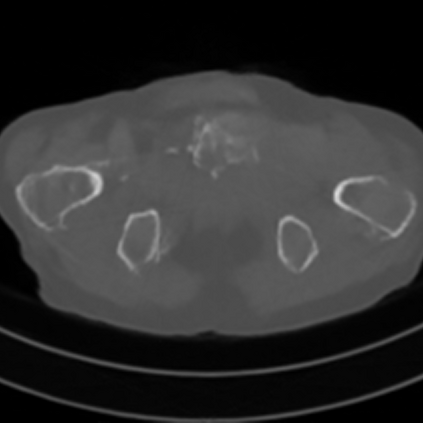

Sparse-view computed tomography (CT) -- using a small number of projections for tomographic reconstruction -- enables much lower radiation dose to patients and accelerated data acquisition. The reconstructed images, however, suffer from strong artifacts, greatly limiting their diagnostic value. Current trends for sparse-view CT turn to the raw data for better information recovery. The resultant dual-domain methods, nonetheless, suffer from secondary artifacts, especially in ultra-sparse view scenarios, and their generalization to other scanners/protocols is greatly limited. A crucial question arises: have the image post-processing methods reached the limit? Our answer is not yet. In this paper, we stick to image post-processing methods due to great flexibility and propose global representation (GloRe) distillation framework for sparse-view CT, termed GloReDi. First, we propose to learn GloRe with Fourier convolution, so each element in GloRe has an image-wide receptive field. Second, unlike methods that only use the full-view images for supervision, we propose to distill GloRe from intermediate-view reconstructed images that are readily available but not explored in previous literature. The success of GloRe distillation is attributed to two key components: representation directional distillation to align the GloRe directions, and band-pass-specific contrastive distillation to gain clinically important details. Extensive experiments demonstrate the superiority of the proposed GloReDi over the state-of-the-art methods, including dual-domain ones. The source code is available at https://github.com/longzilicart/GloReDi.